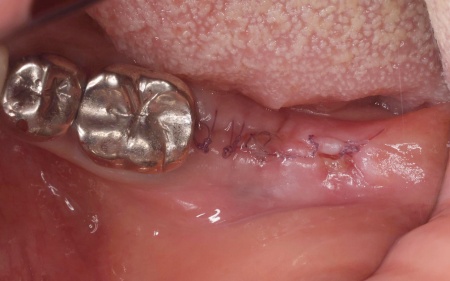

経過観察後、骨の状態が安定したことを確認したら、インプラント体(人工歯根)を顎の骨に埋め込む手術を行います。

手術では、歯茎を切開した骨を露出させ、専用の器具で慎重に穴を形成したうえでインプラント体を埋入します。続いて歯茎を縫合し、インプラント体が骨と結合するまでの期間を設けました。

インプラント体と骨の結合を確認しました。